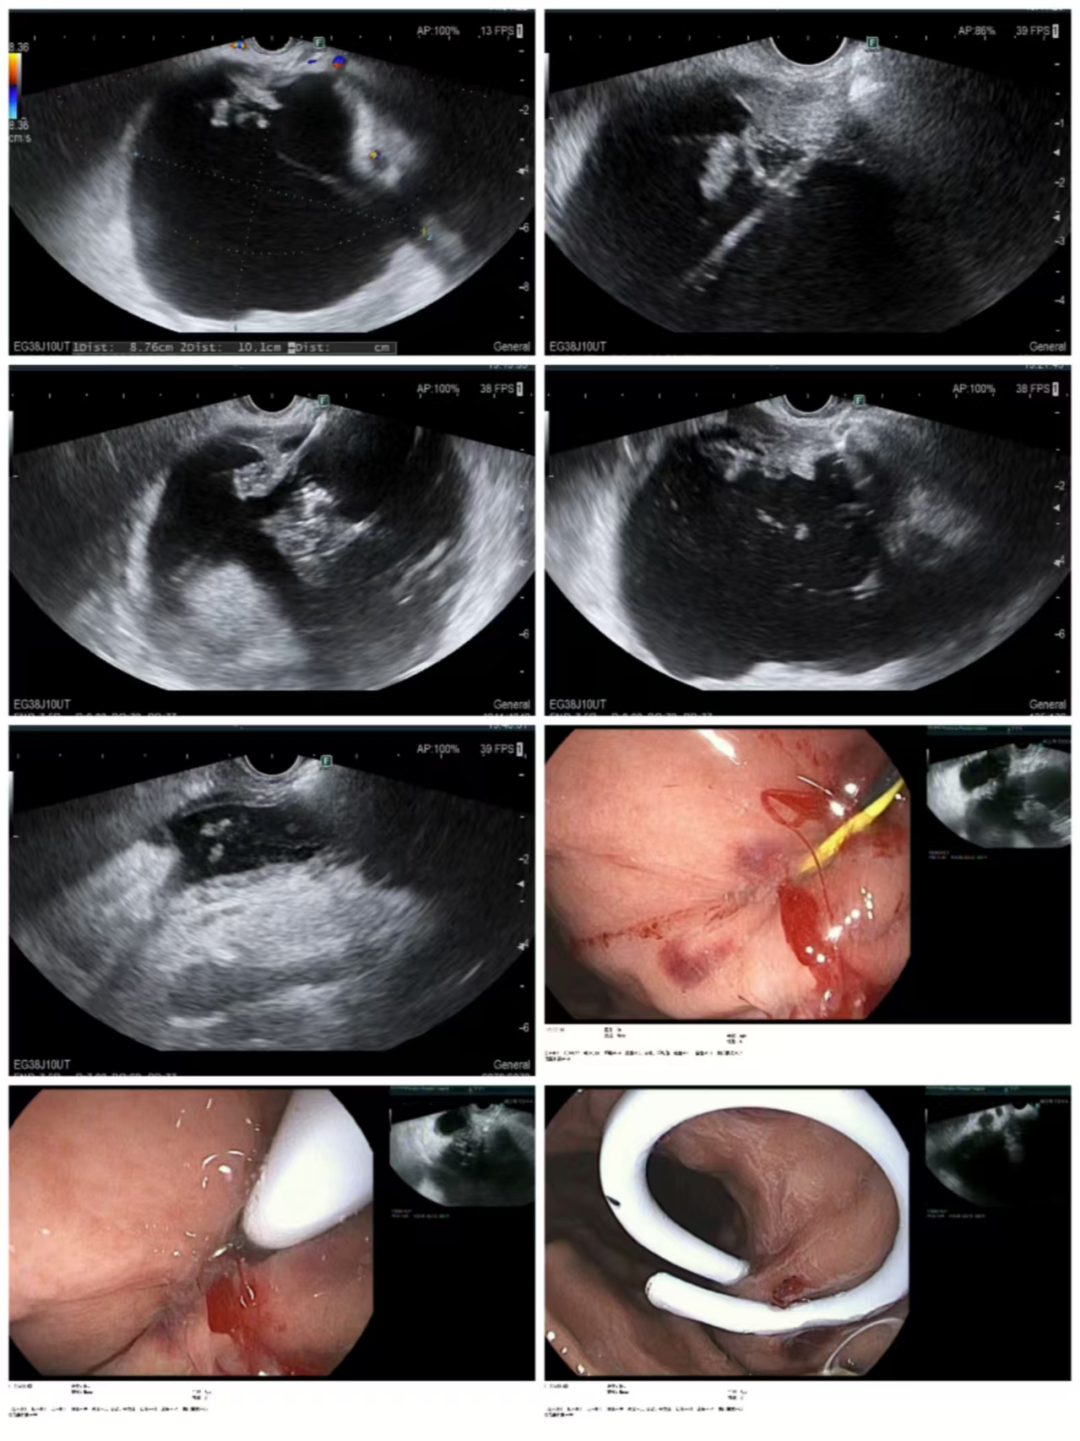

患者为青年男性,因“上腹部持续性胀痛2天”入住我院普外一病区,腹部增强CT检查提示:考虑急性胰腺炎并假性囊肿形成,胰胃间隙存在一直径约10厘米的假性囊肿,已对周围脏器形成明显压迫,引发腹胀不适。如不及时干预,囊肿可能继续增大、引发感染甚至破裂,危及患者健康。

患者术前CT

本次手术在刘哲教授指导下完成,刘哲通过超声内镜扫查胰腺:胰胃间隙可见一巨大囊性病变,较大长径约10.1cm,其内可见点片状高回声信号,彩色多普勒显示内部未见明显血流信号,采用一次性囊肿切开刀于胃体上段大弯侧电切电凝后;进入囊肿腔内,引入导丝,通过一次性囊肿切开刀再次扩大切口,抽出淡褐色液体送常规、生化、淀粉酶、肿瘤标记物及培养,经斑马导丝置入10Fr双猪尾支架1根及鼻胆管一根于囊腔内,随后超声评估支架及鼻胆管位于囊腔内,可见囊腔明显缩小,穿刺道未见活动性出血。实现了超声实时引导,安全穿刺,双路引流设计,提升疗效,该术式尤其适合囊肿较大、感染风险高的病例,体现我院在处理复杂性囊肿中的个体化策略能力。